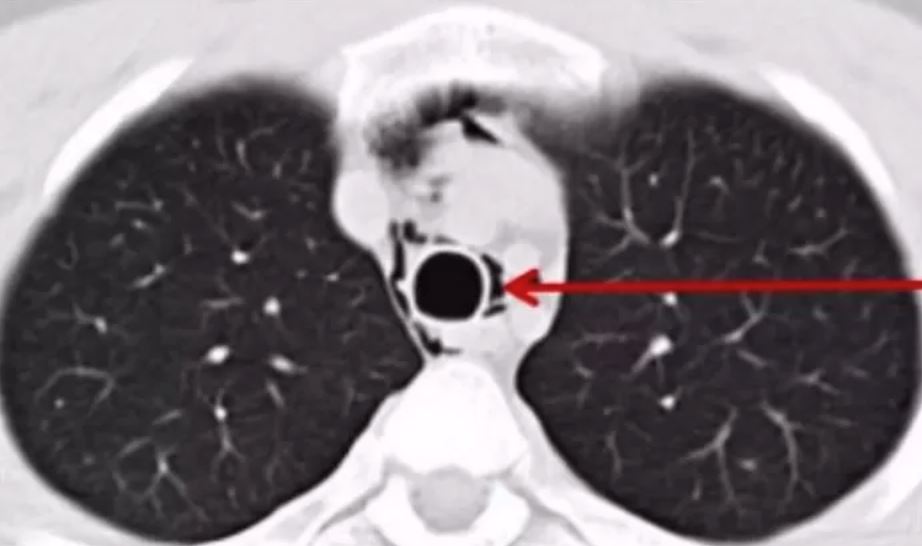

Setelah tiba di bilik kecemasan hospital tempatan, doktor mendiagnosnya mengalami pneumotoraks, juga dikenali sebagai "paru-paru runtuh".

Pneumotoraks merujuk kepada keadaan udara yang tidak normal di antara paru-paru dan dinding dada. Ia boleh disebabkan oleh pelbagai faktor seperti kecederaan dada, penyakit paru-paru, atau pecahnya alveolus disebabkan oleh tekanan yang tiba-tiba atau berlebihan.

Dalam kes ini, doktor percaya bahawa jeritan kuat lelaki muda tersebut semasa konsert menyebabkan pecahnya alveolus pada salah satu paru-parunya.